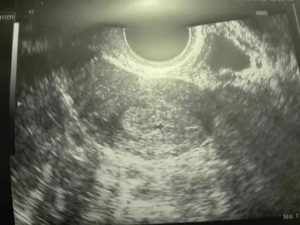

На 10-14 неделе беременности женщина проходит ультразвуковое исследование, позволяющее врачу сделать замеры плодного яйца для установления точного срока гестации. Иногда в ходе обследования обнаруживается деформированное плодное яйцо. Основной причиной этой патологии считается повышение тонуса матки.

При нормальном наступлении беременности околоплодное яйцо располагается в матке. На маленьком сроке, в 5-6 недель оно становится округлым или каплевидным. К 6-7 неделям на продольном скане УЗИ яйцо выглядит овальным, а на поперечном сохраняет округлость. Если же обследование показывает приплюснутость плодного яйца по бокам и отсутствие овальной формы, значит матка находится в тонусе.

Чем может грозить изменение форм и размеров околоплодного яйца? Сильное превышение или уменьшение его размеров свидетельствует о замирании беременности, но, как правило, врач продолжает наблюдения, контролируя динамику развития изменений. О замершей беременности говорит и вытянутое плодное яйцо.

При увеличении тонуса матки углы оболочки яйца выглядят неровными. В большинстве случаев врачи считают такие изменения безобидными, если только они не сопровождаются раскрытием шейки, темными выделениями и болями. При подобных симптомах появляется реальная угроза потери плода.

Низкое положение плодного яйца в полости матки требует постоянного контроля. Если оно очень близко подходит к шейке матки, врач может принять решение о его удалении. При внематочной беременности УЗИ показывает, что плодное яйцо не содержит эмбриона, вместо него в полости яйца присутствуют жидкость и сгустки крови.